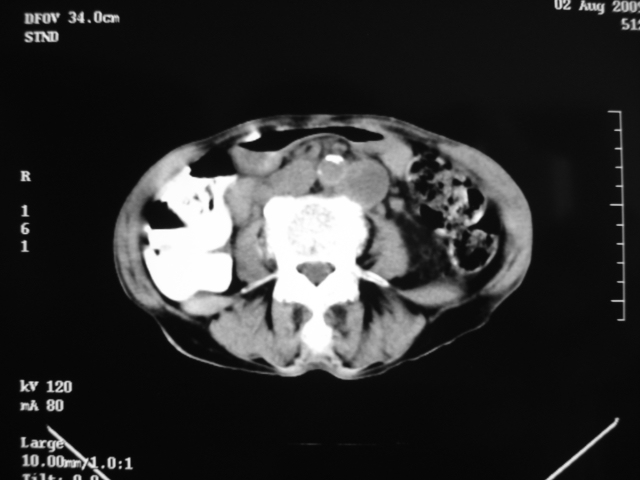

同事奶奶,73岁,腹痛一年,夜晚较重,潜血+++,拒绝增强,考虑左肾ca并腹膜后转移;请各位老师帮忙看看,谢谢!

左肾癌侵及输尿管上段,腹膜后多发淋巴结转移,脾脏钙化灶。至于潜血+++,要考虑消化道病变,本次ct片肠腔未见明显异常。

1)考虑左肾癌侵犯肾盂并腹膜后淋巴结转移。2)脾脏钙化灶。

考虑左肾癌侵犯肾盂并腹膜后淋巴结转移。